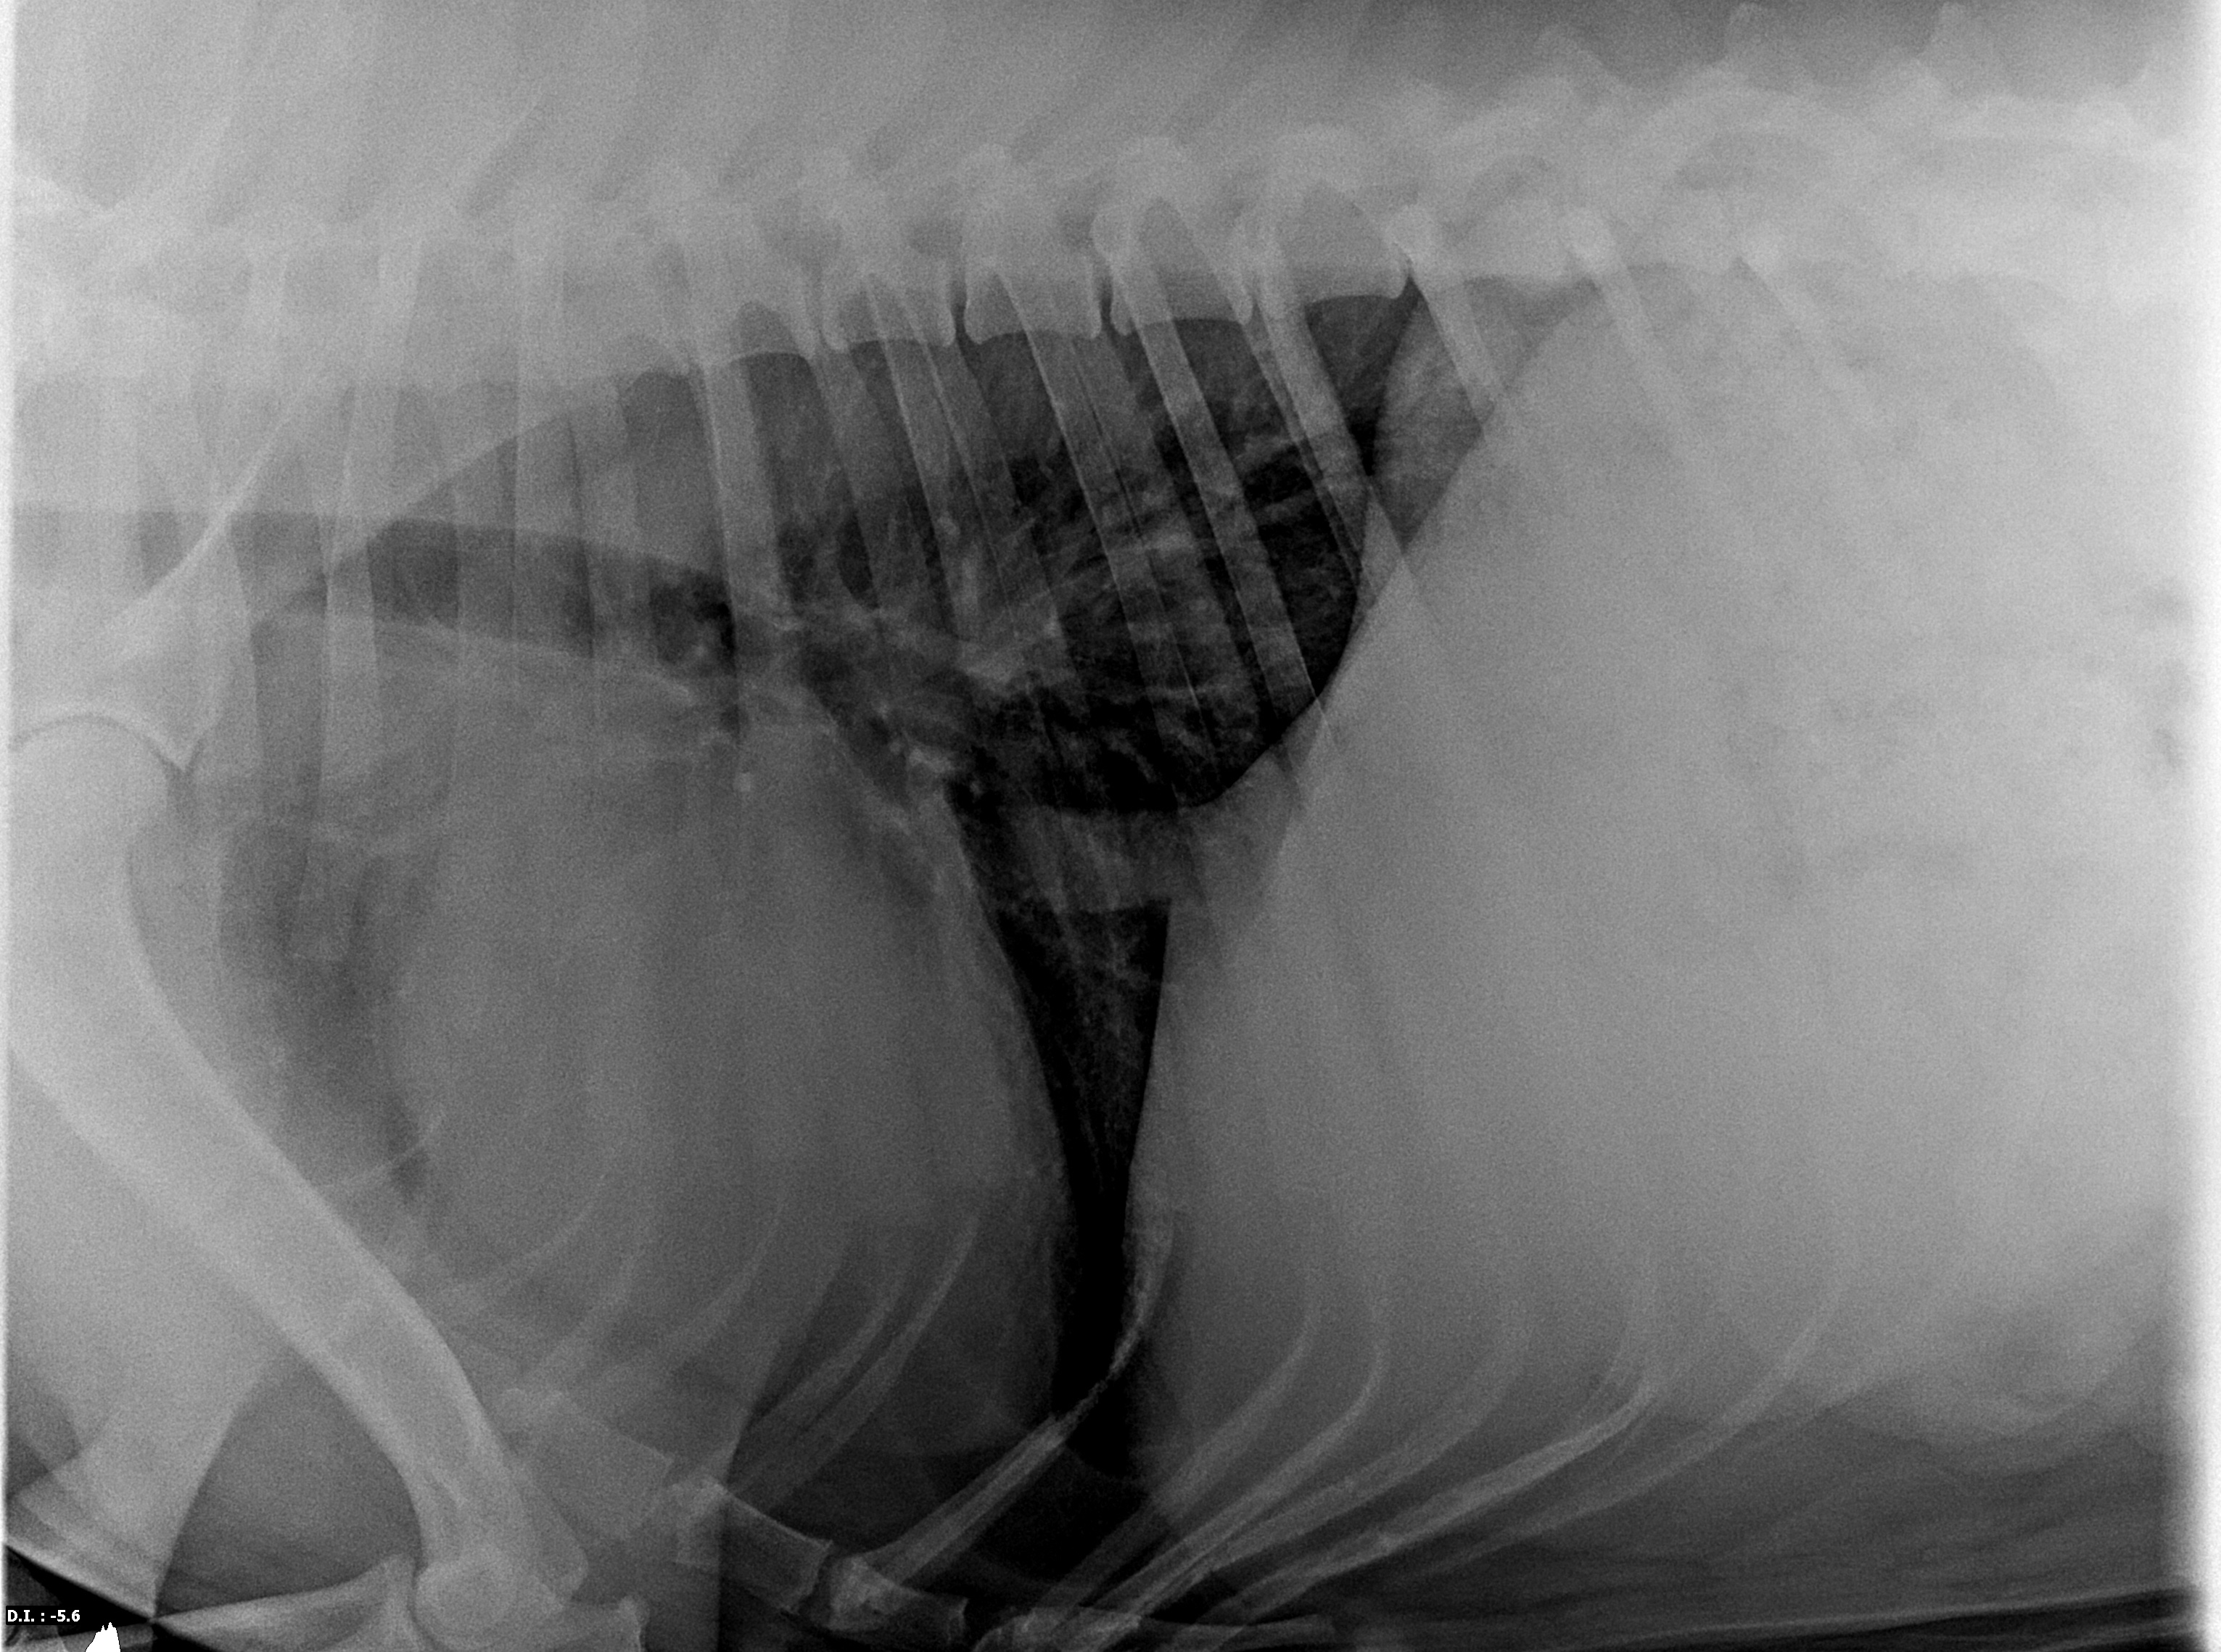

Dobry den, u nasi fenky jsme vypozorovali zrychlene dyhani, ihned jsme tedy navstivili veterinare a ten nam po rtg vysetreni sdelil, ze ma nase 2,5 rocni fenka plice cca na 8 let. Chtel bych se zeptat je tohle vubec mozne? Nedokazu si predstavit jak k tomu mohlo dojit, nikdy nemela zadny kasel atd.. dostava tu nejlepsi peci co jsme schopni ji dat vcetne premioveho krmiva atd.. veteeinarka nam sdelila, ze neni schopna poznat z ceho to konrketne je a ihned po nas chtela dalsi vysetreni za x tisic.. je pravda ze nase fenka moc nespolupracuje a kdyz na ni sahne nekdo cizi tak ihned vrci, takze si ji lekarka ani nemohla poslechnout.. ale zarazi me ze veterinarka neni schopna aspon priblizne diagnostikovat proc tomu tak je.. nevim jak mam dal postupovat a proto pisu sem.. skutecne jsou plice tak “stare”? Nize pridavam rtg snimky.. predem moc dekuji za odpoved, Novak

Dobrý den, pane Nováku. Pokud je jediný problém, že fena zrychleně dýchá, je mnoho možných příčin, které toto způsobují, včetně metabolických onemocnění a podobně. Je potřeba fenku kompletnš vyšetřit, doptat se na různé detaily, zvážit nutná vyšetření. Nemohu Vám tedy takto říci, co fence je. Rentgen je trochu špatně napolohovaný, neboť přední končetina výrazně zasahuje do plicního a srdečního pole, což ztěžuje interpretaci. Ve zbytku snímku žádnou patologii neporozuji, definici "plíce na 8 let" neznám a pokud Vám Váš veterinář není schopen uspokojivě vysvětlit svoje domněnky a stanovit diagnózu, nemohu Vám doporučit než navštívit jiného. Přeji hodně zdraví, věřím, že důvod a řešení existuje.